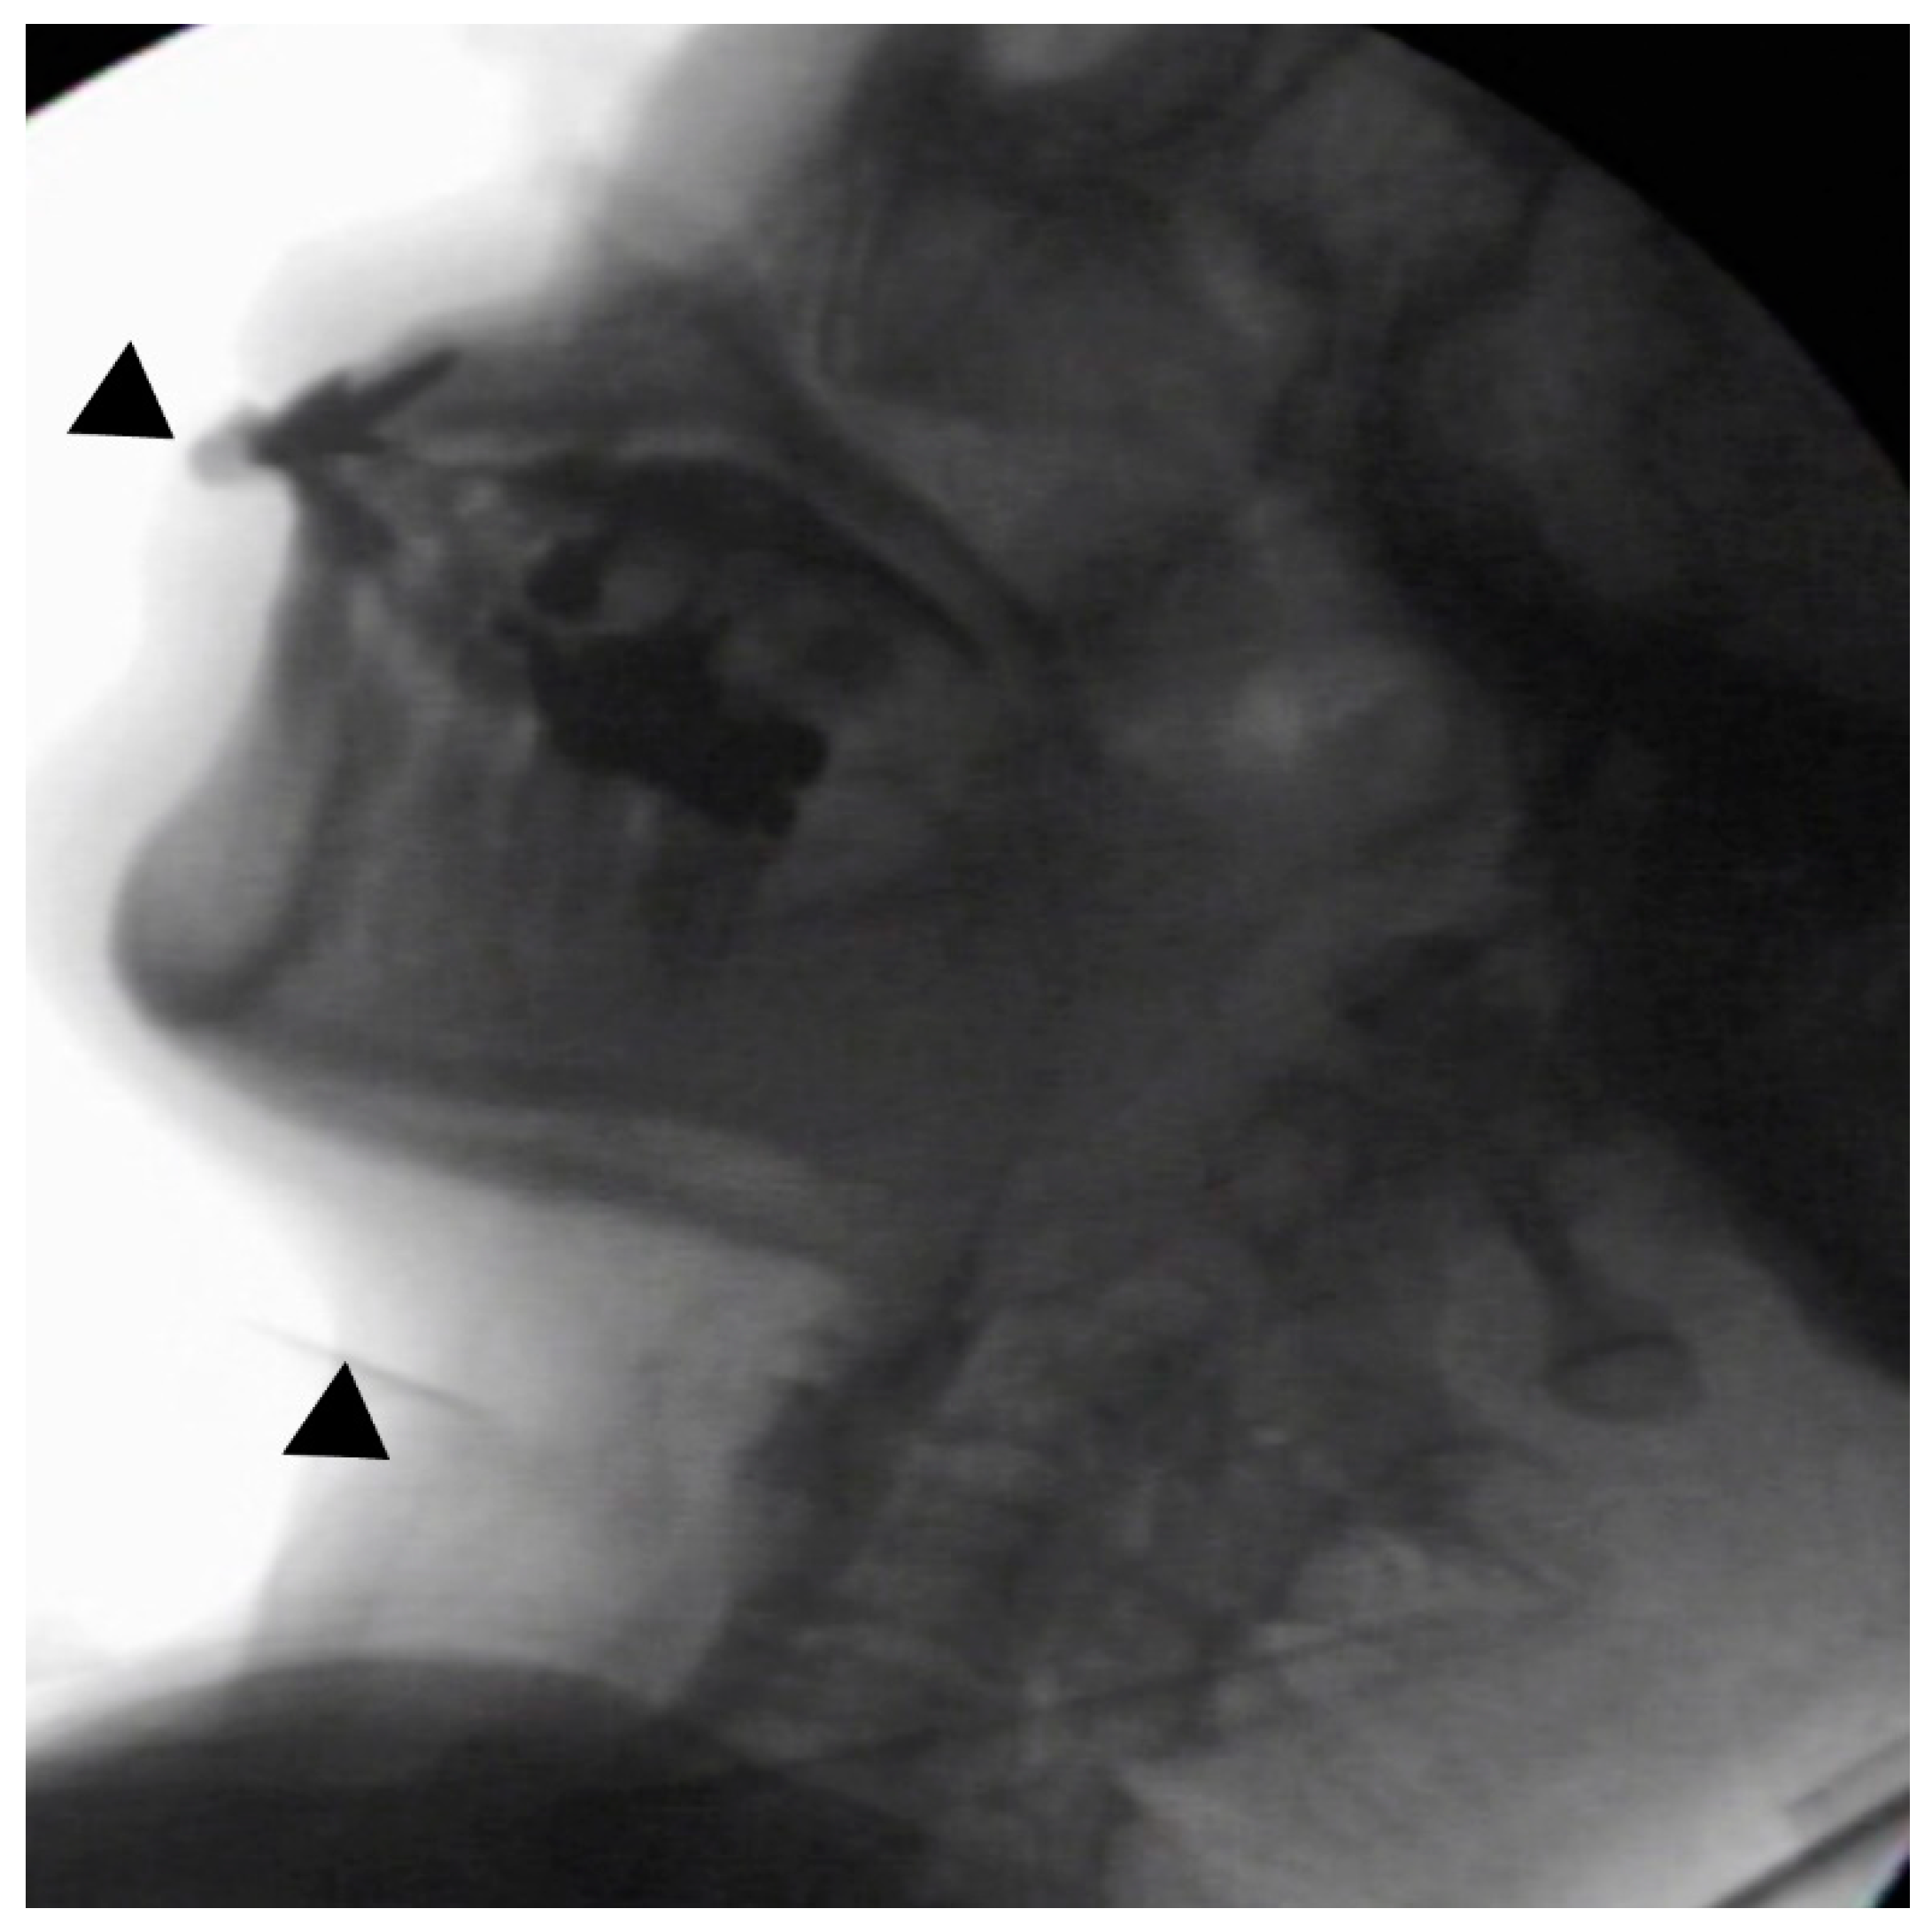

In the seated position, spoon-feeding was infeasible and bolus transport did not occur; furthermore, anterior–posterior tongue movement caused most of the food to dribble out of her mouth. After placing food on top of her tongue using a tube-fitted syringe, most still dribbled out of her mouth (Figure 1a); however, a proportion was transported into the pharynx (Figure 1b). Furthermore, after placing food at the back of her tongue with the patient reclined at 30°, a small amount still dribbled out of her mouth; however, the patient could swallow without aspiration (Figure 2). After increasing the amount placed in her mouth at one time to 7 mL, more food dribbled out of her mouth (Figure 3); additionally, there was a decreased amount transported to the pharynx. When 5 mL of a moderately thick paste was placed in her mouth, none of it dribbled out; however, slight silent aspiration was present (Figure 4). There were no particular issues observed due to peristalsis from the upper esophagus to the stomach.

Figure 2.

The patient was reclined at 30° for the administration of 5 mL of an extremely thick paste. Oral transport was better than in the sitting position; furthermore, a little of the food dribbled out of the mouth (above ▲), and no aspiration occurred (below ▲).